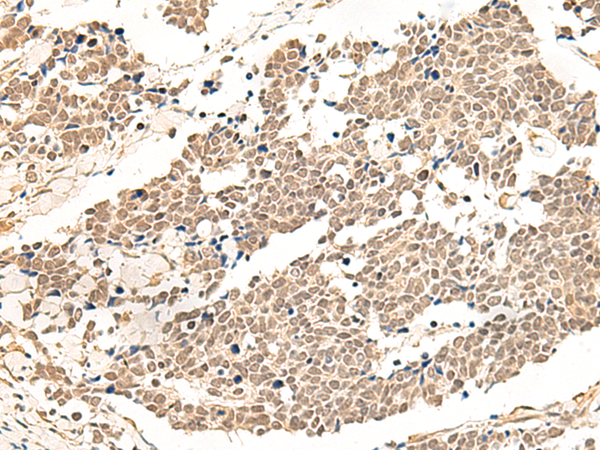

IHC positive control:

Human lung cancer and Human prostate cancer